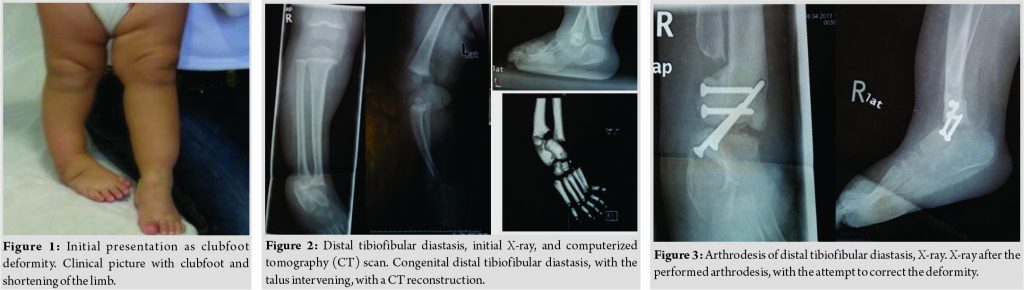

A 3-month-old baby was initially referred to our hospital, on October 2007, for evaluation of the right side clubfoot that was treated in another hospital, with serial casting (Fig. 1). He was the first child of apparently healthy and young parents, after a normal 36 weeks pregnancy. He had normal motor development; there were no other deformities. He had a stiff right side clubfoot, with apparent shortening of the leg. He had a short 1st ray of the foot. Radiological examination confirmed the diagnosis of the distal tibiofibular diastasis. His parents went abroad to North Europe, where initial treatment was provided with serial casting and closed tenotomy of the Achilles tendon, improving the shape and the position of the foot. At the age of 18 months, he was brought for a new clinical and radiological evaluation. There was still a stiff equinus and varus position of the foot and LLD. X-ray examination showed the diastasis of the distal tibiofibular joint, with the talus intervening. There was shortening of the tibia (Fig. 2).

The child was surgically treated at 4 years of age, in the same hospital abroad, where a distal tibiofibular synostosis and arthrodesis of the ankle joint were performed. The metalwork was removed 3 years later and an attempt to correct the valgus position of the knee was done with a plate at the medial growth plate of the distal femur (Fig. 3). The child returned to our hospital 8 years later, on February 2016, for another evaluation. He had completely stiff foot in varus and equinus, (30 d varus and 20d equinus), with a severe shortening of the limb.